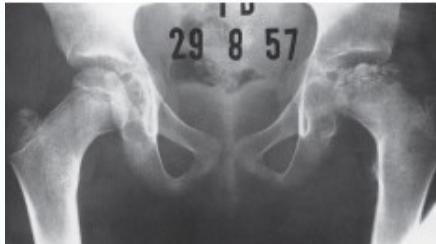

Radiographic Stages:

-

Initial/ Bone Death Stage - May initially appear normal on x-ray

- Increased density followed by collapse

Revascularization and Repair Stage - Reduced density and fragmentation on x-ray

Distortion and Remodeling Stage - Distortion, flattening (coxa plana)

- Enlargement (coxa magna) with partial uncoverage

Radiological Progression:

Progression: Sclerosis → Collapse → Fragmentation → Remodeling

Imaging Examples: